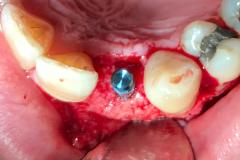

Immediate implant placement with simultaneous bone augmentation and connective tissue grafting. The case will be completed with crown lengthening, veneer replacement, and soft tissue optimisation to achieve ideal emergence profiles.

Immediate implant placement following extraction, combined with bone augmentation and connective tissue grafting to support optimal healing and soft tissue stability. This approach helps preserve natural contours and provides a strong foundation for a highly aesthetic final restoration.